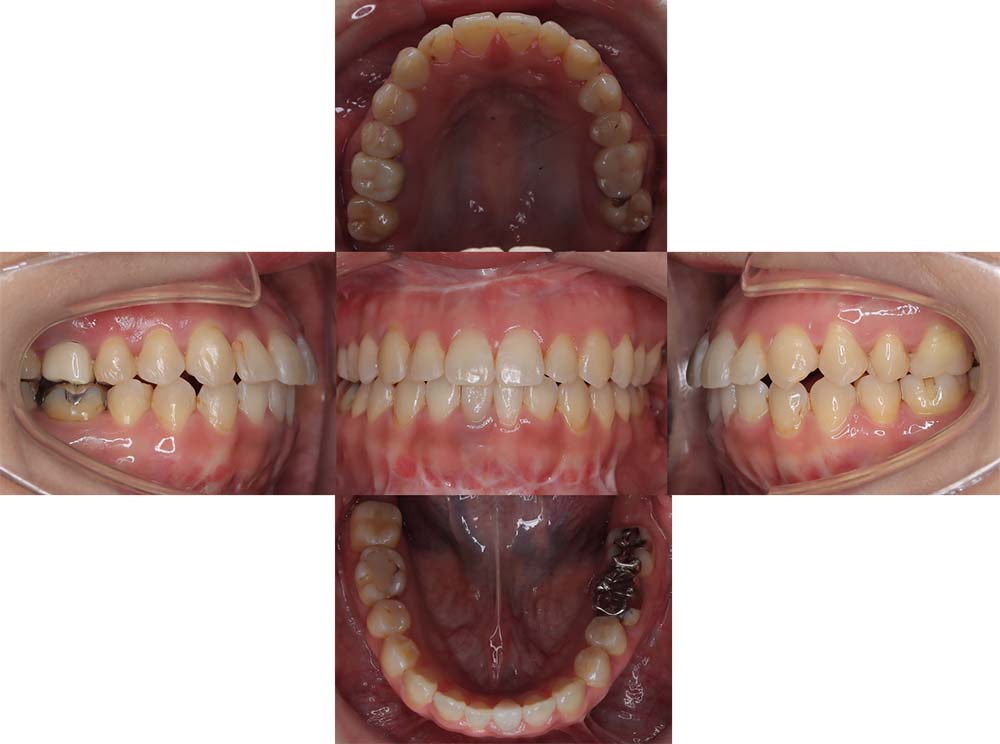

症例04

| 主訴 | 歯並びのガタガタと出っ歯が気になる。 |

| 診断名あるいは主な症状 | 上顎前突、叢生 |

| 年齢/性別 | 16歳・女性 |

| 矯正ステージ | 大人の矯正治療 |

| 治療方法 | ワイヤー矯正 |

| 抜歯部位/抜歯有無 | 抜歯 |

| 治療内容 | 抜歯したスペースを使用し、ガタガタの改善と上下顎前歯を後退させた。 |

| 費用 |

85万円程度(2025.10時点の料金となります。) ※矯正基本料金、審美ブラケットを含む |

| 治療期間 | 2年5ヶ月 |

| 主なリスク・副作用 | 痛み、歯根吸収、歯肉退縮、虫歯、後戻り |